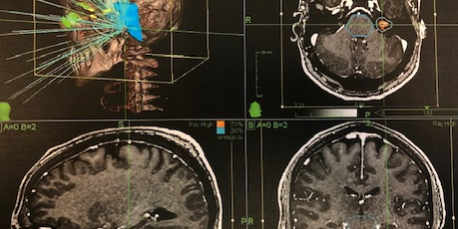

Ενδοκαναλικό Ακουστικό Νευρίνωμα αριστερά